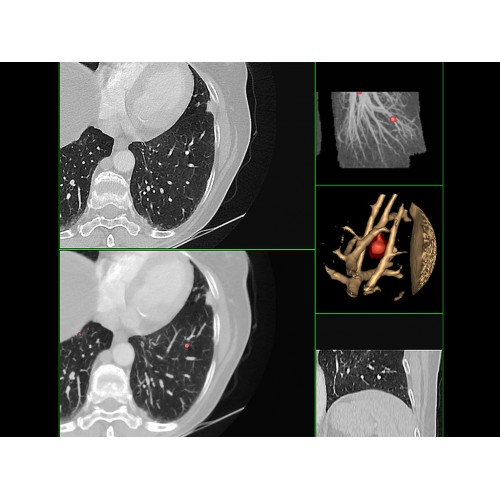

Онкология

• Раннее выявление новообразований и контроль эффективности лечения.

• Планирование лучевой терапии с высокой точностью.

КТ-аппараты, Ветеринарные аппараты КТ, Аппараты КТ для легких